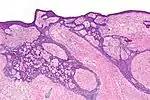

High-magnification micrograph of basal-cell carcinoma.

Basal-cell carcinoma cells appear similar to epidermal basal cells, and are usually well differentiated.[15]

Nodular basal-cell carcinoma (also known as "classic basal-cell carcinoma") accounts for between 50% and 80% of all BCC.[2] It most commonly occurs on the sun-exposed areas of the head and neck.[2] Histopathology shows aggregates of basaloid cells with well-defined borders, showing a peripheral palisading of cells and one or more typical clefts.[17] Such clefts are caused by shrinkage of mucin during tissue fixation and staining.[18] Central necrosis with eosinophilic, granular features may be also present, as well as mucin. The heavy aggregates of mucin determine a cystic structure. Calcification may be also present, especially in long-standing lesions.[17] Mitotic activity is usually not so evident, but a high mitotic rate may be present in more aggressive lesions.[17] Adenoidal BCC can be classified as a variant of NBCC, characterized by basaloid cells with a reticulated configuration extending into the dermis.[17]